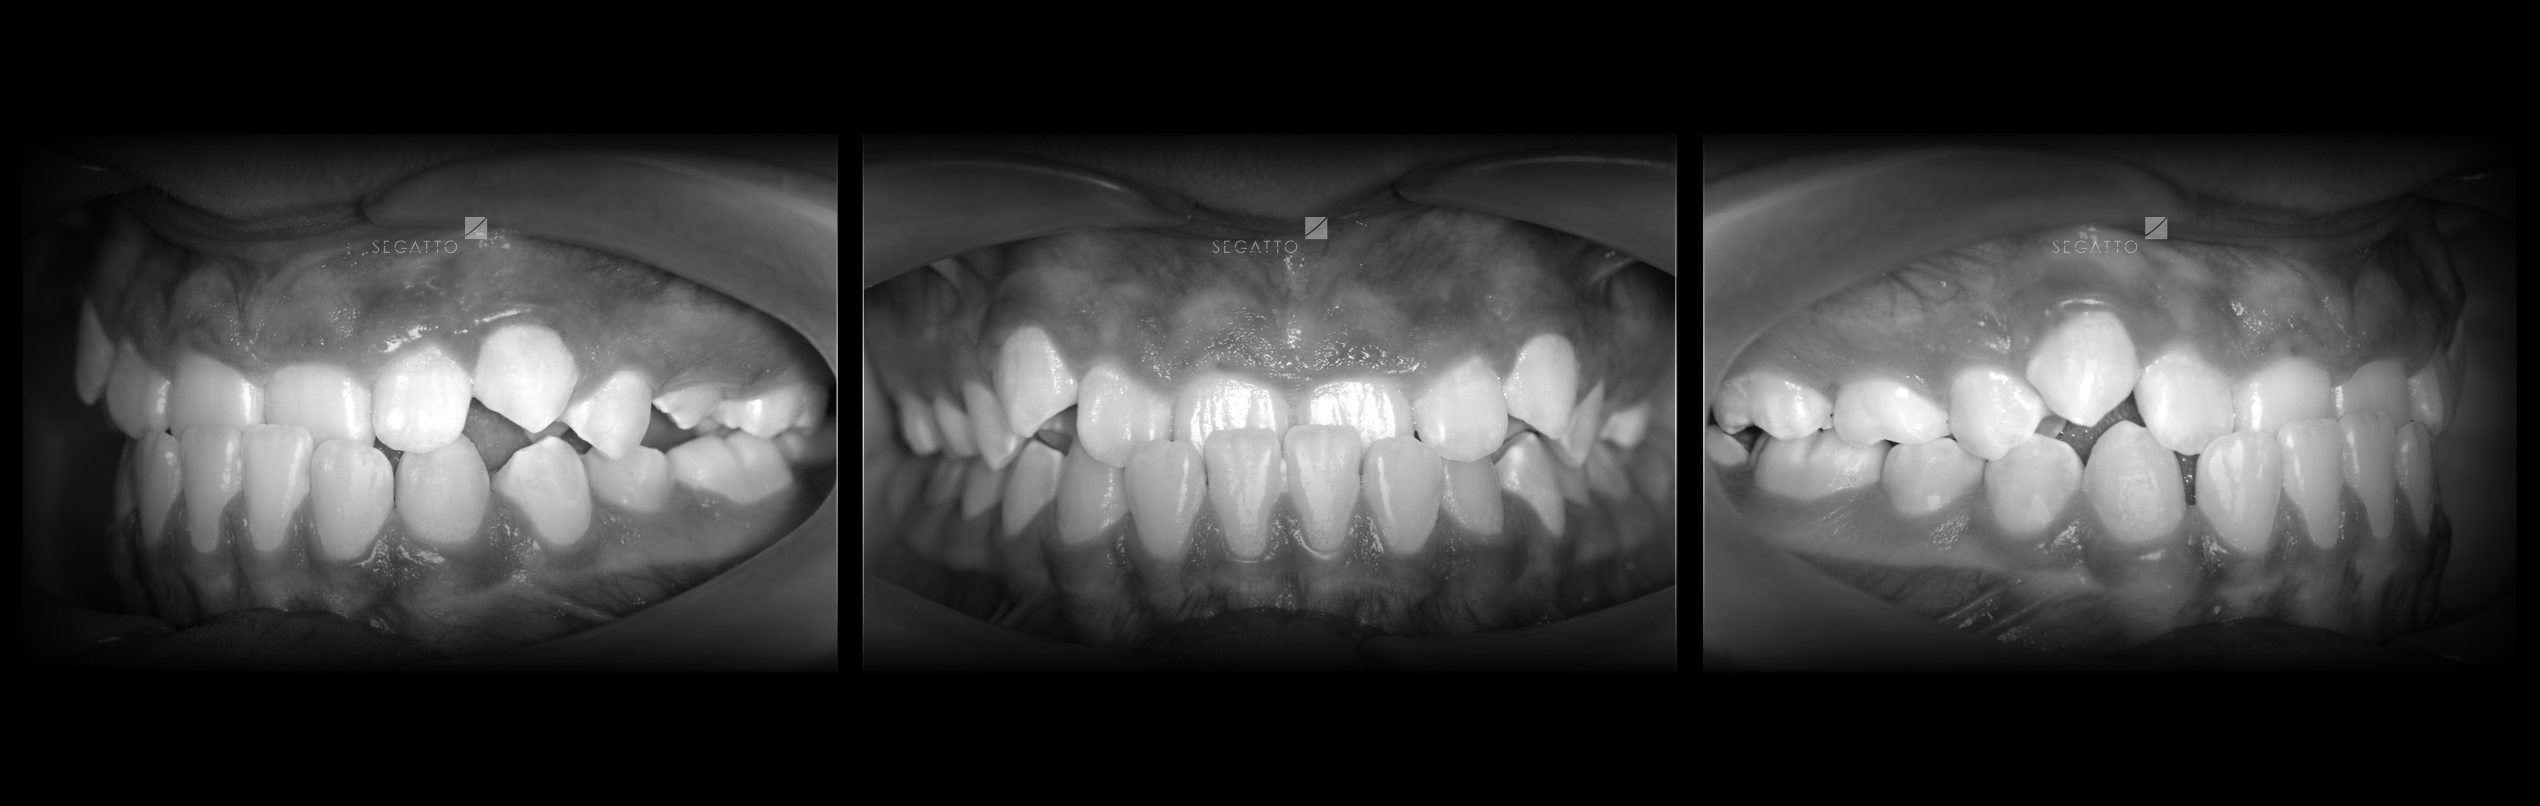

Orthodontics

Cases